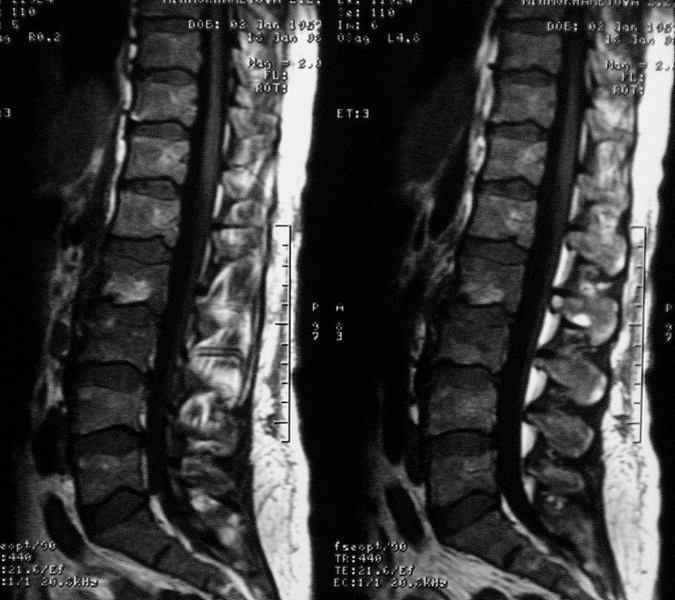

Отправляю MRI в динамике, снятые с пленки на фотоаппарат.

Имя     : при__госпитализации.jpg